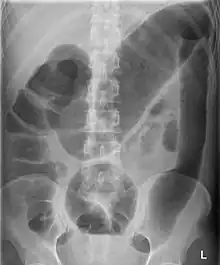

Colectasie ou mégacôlon visible sur un ASP dans le cadre d'une rectocolite hémorragique.

La colectasie (aussi appelée mégacôlon) est une dilatation massive du côlon gauche ou transverse, de plus de 6 cm, ou du cæcum de plus de 10 cm sans obstruction mécanique.